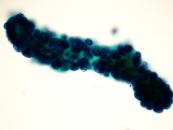

第38回日本臨床細胞学会九州連合会学会(熊本)スライドカンファレンス症例3

種別:消化器・口腔

出題:甲斐 敬太 佐賀大学医学部附属病院病理部

| 年齢 | 60代 | 性別 | 男性 |

|---|---|---|---|

| 採取部位 | 胆汁 | 採取方法 | 経皮経肝胆道ドレナージ |

| 検体処理法 |

臨床所見

既往歴:潰瘍性大腸炎治療中。

現病歴:難治性の十二指腸潰瘍を合併し、通過障害をきたしていた。閉塞性黄疸が出現し、精査で原発性硬化性

胆管炎が疑われた。減黄目的に経皮経肝胆道ドレナージが行われ、胆汁が提出された。なお、狭窄部の

胆管と十二指腸潰瘍部から生検が行われたが、悪性所見は指摘できなかった。

| 正解 | 5.腺癌 |

▼選択肢及び投票結果

| 1.急性胆管炎 (反応性異型) | 1件 | (1.0%) | |

| 2.原発性硬化性胆管炎 (反応性異型) | 25件 | (24.0%) | |

| 3.Low-grade BilIN | 31件 | (29.8%) | |

| 4.Low-grade IPNB | 19件 | (18.3%) | |

| 5.腺癌 | 28件 | (26.9%) | |

| 投票総数 | 104件 | (100%) |